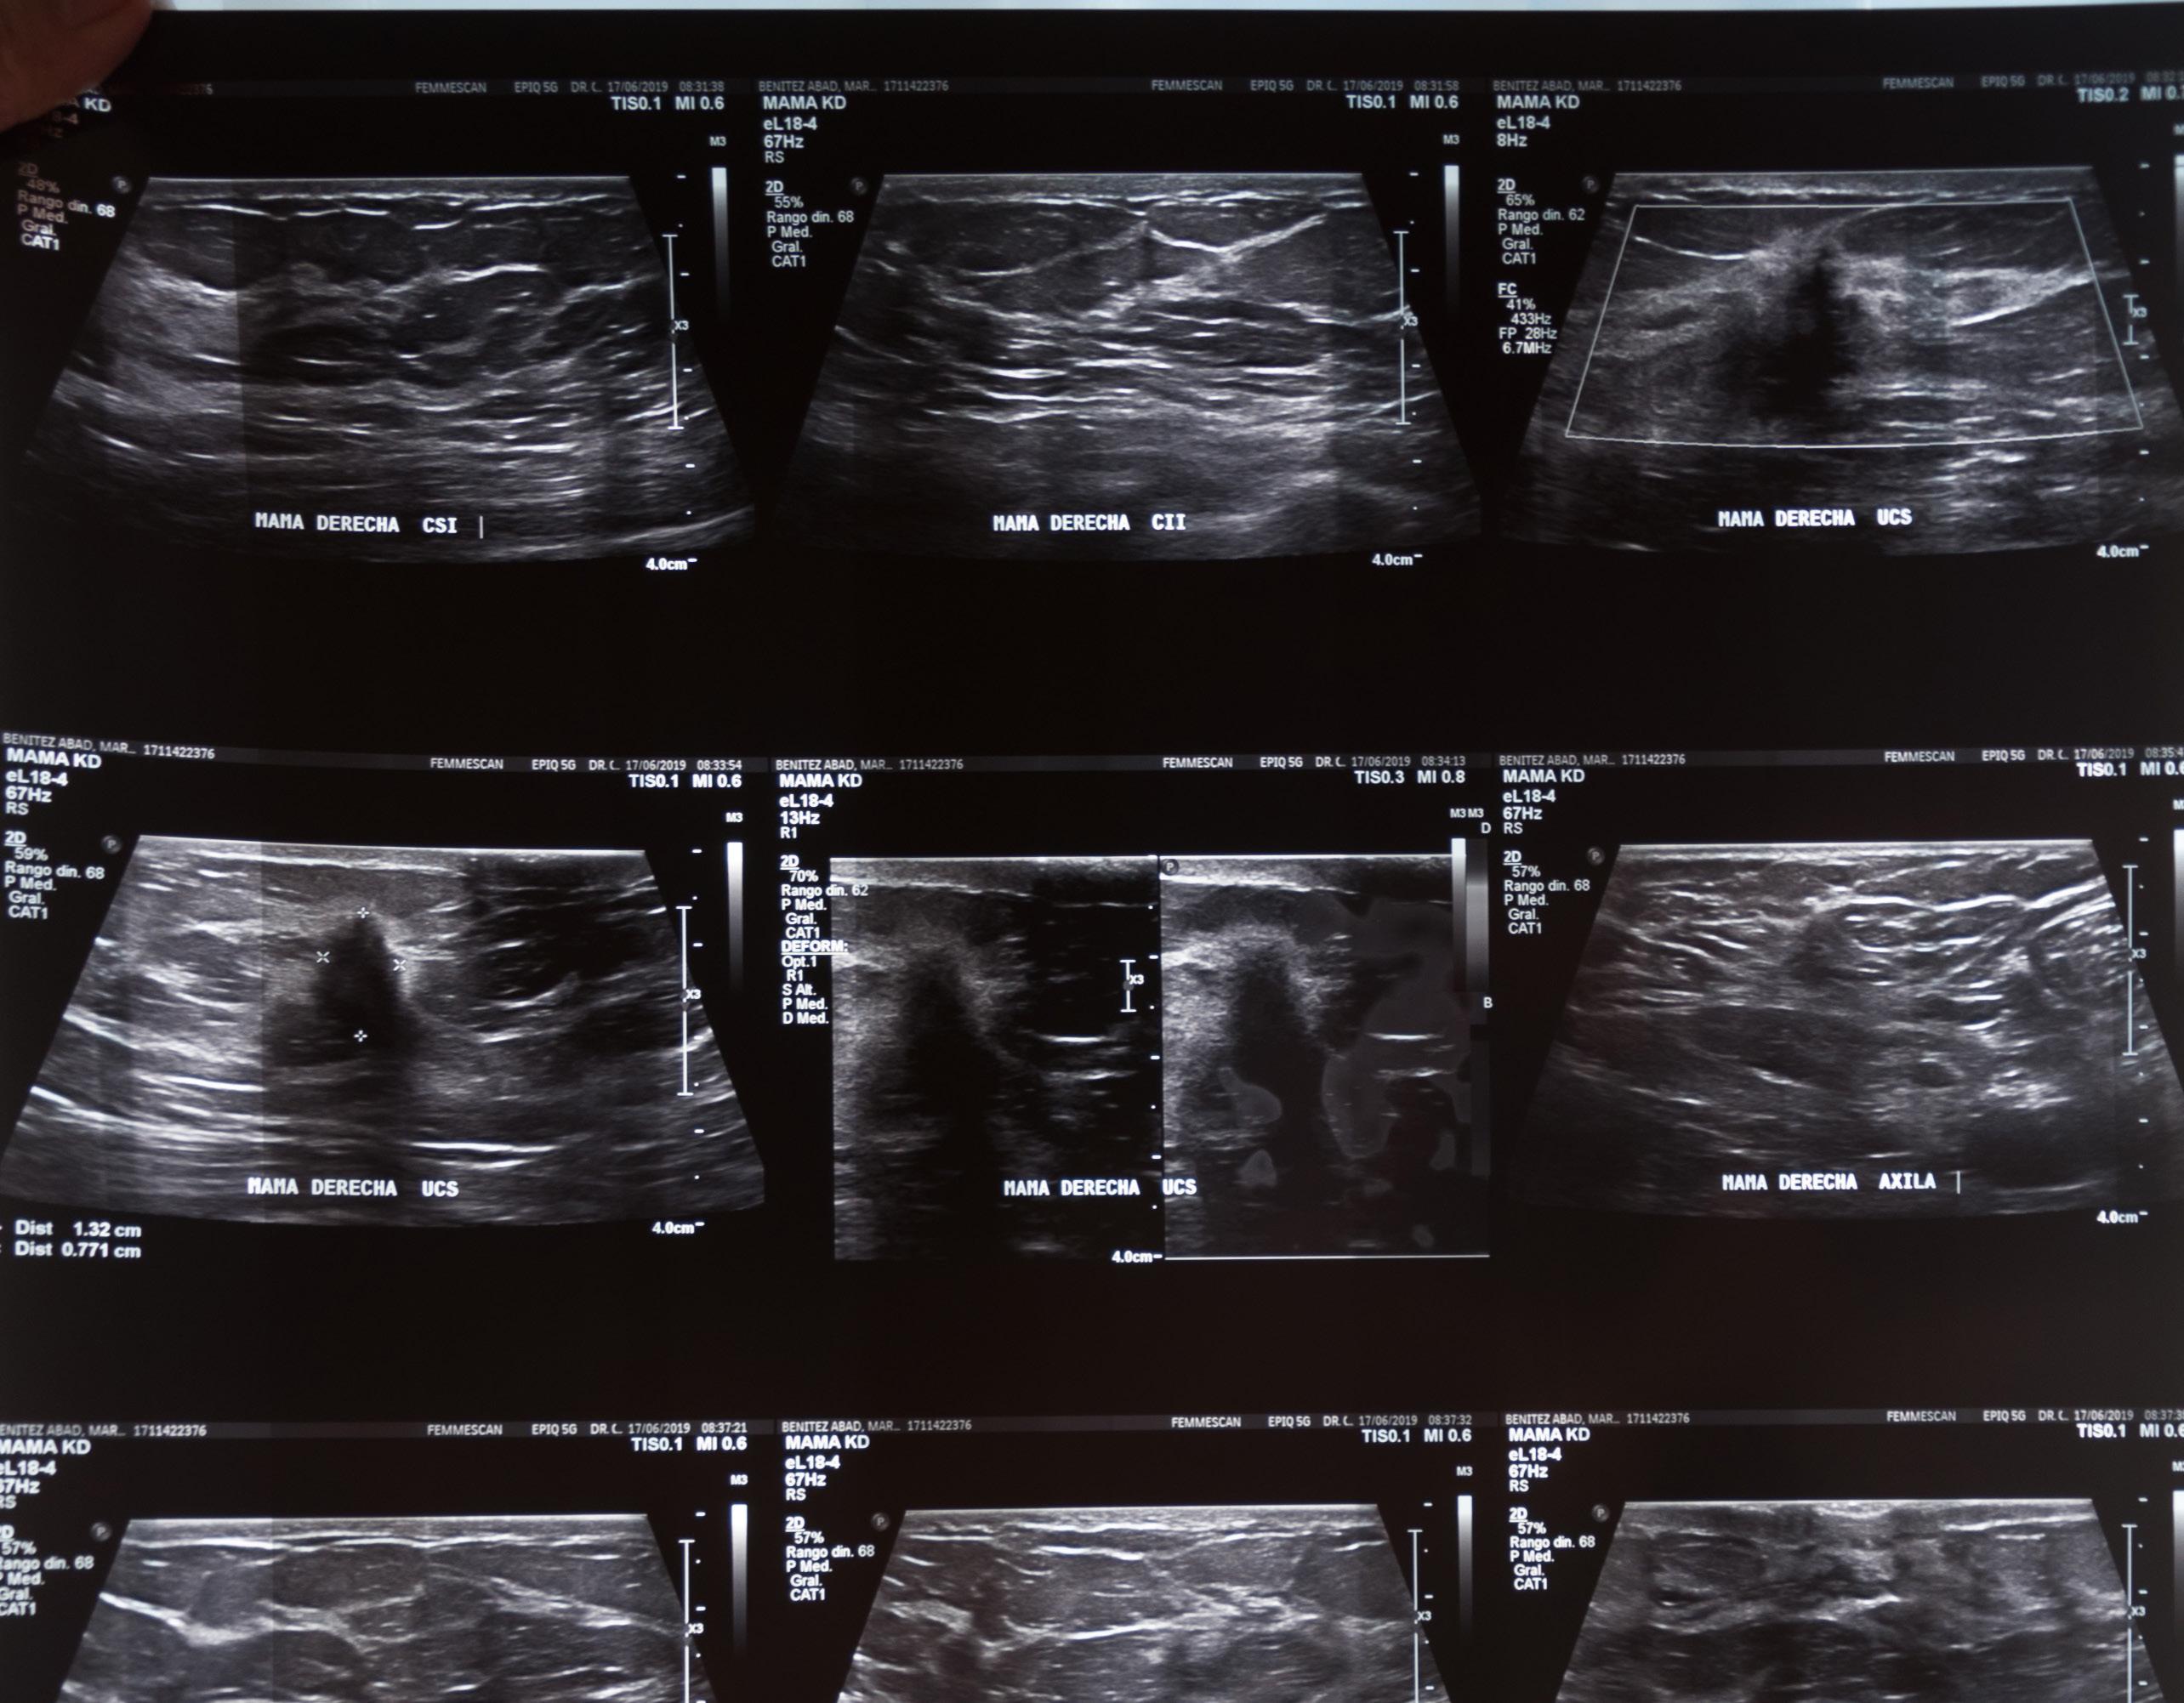

Carpetas con exámenes, recetas, ecografías, facturas de los tratamientos de Gabriela para el cáncer de mama. Quito, Ecuador.

Fotografía: Camila Arellano